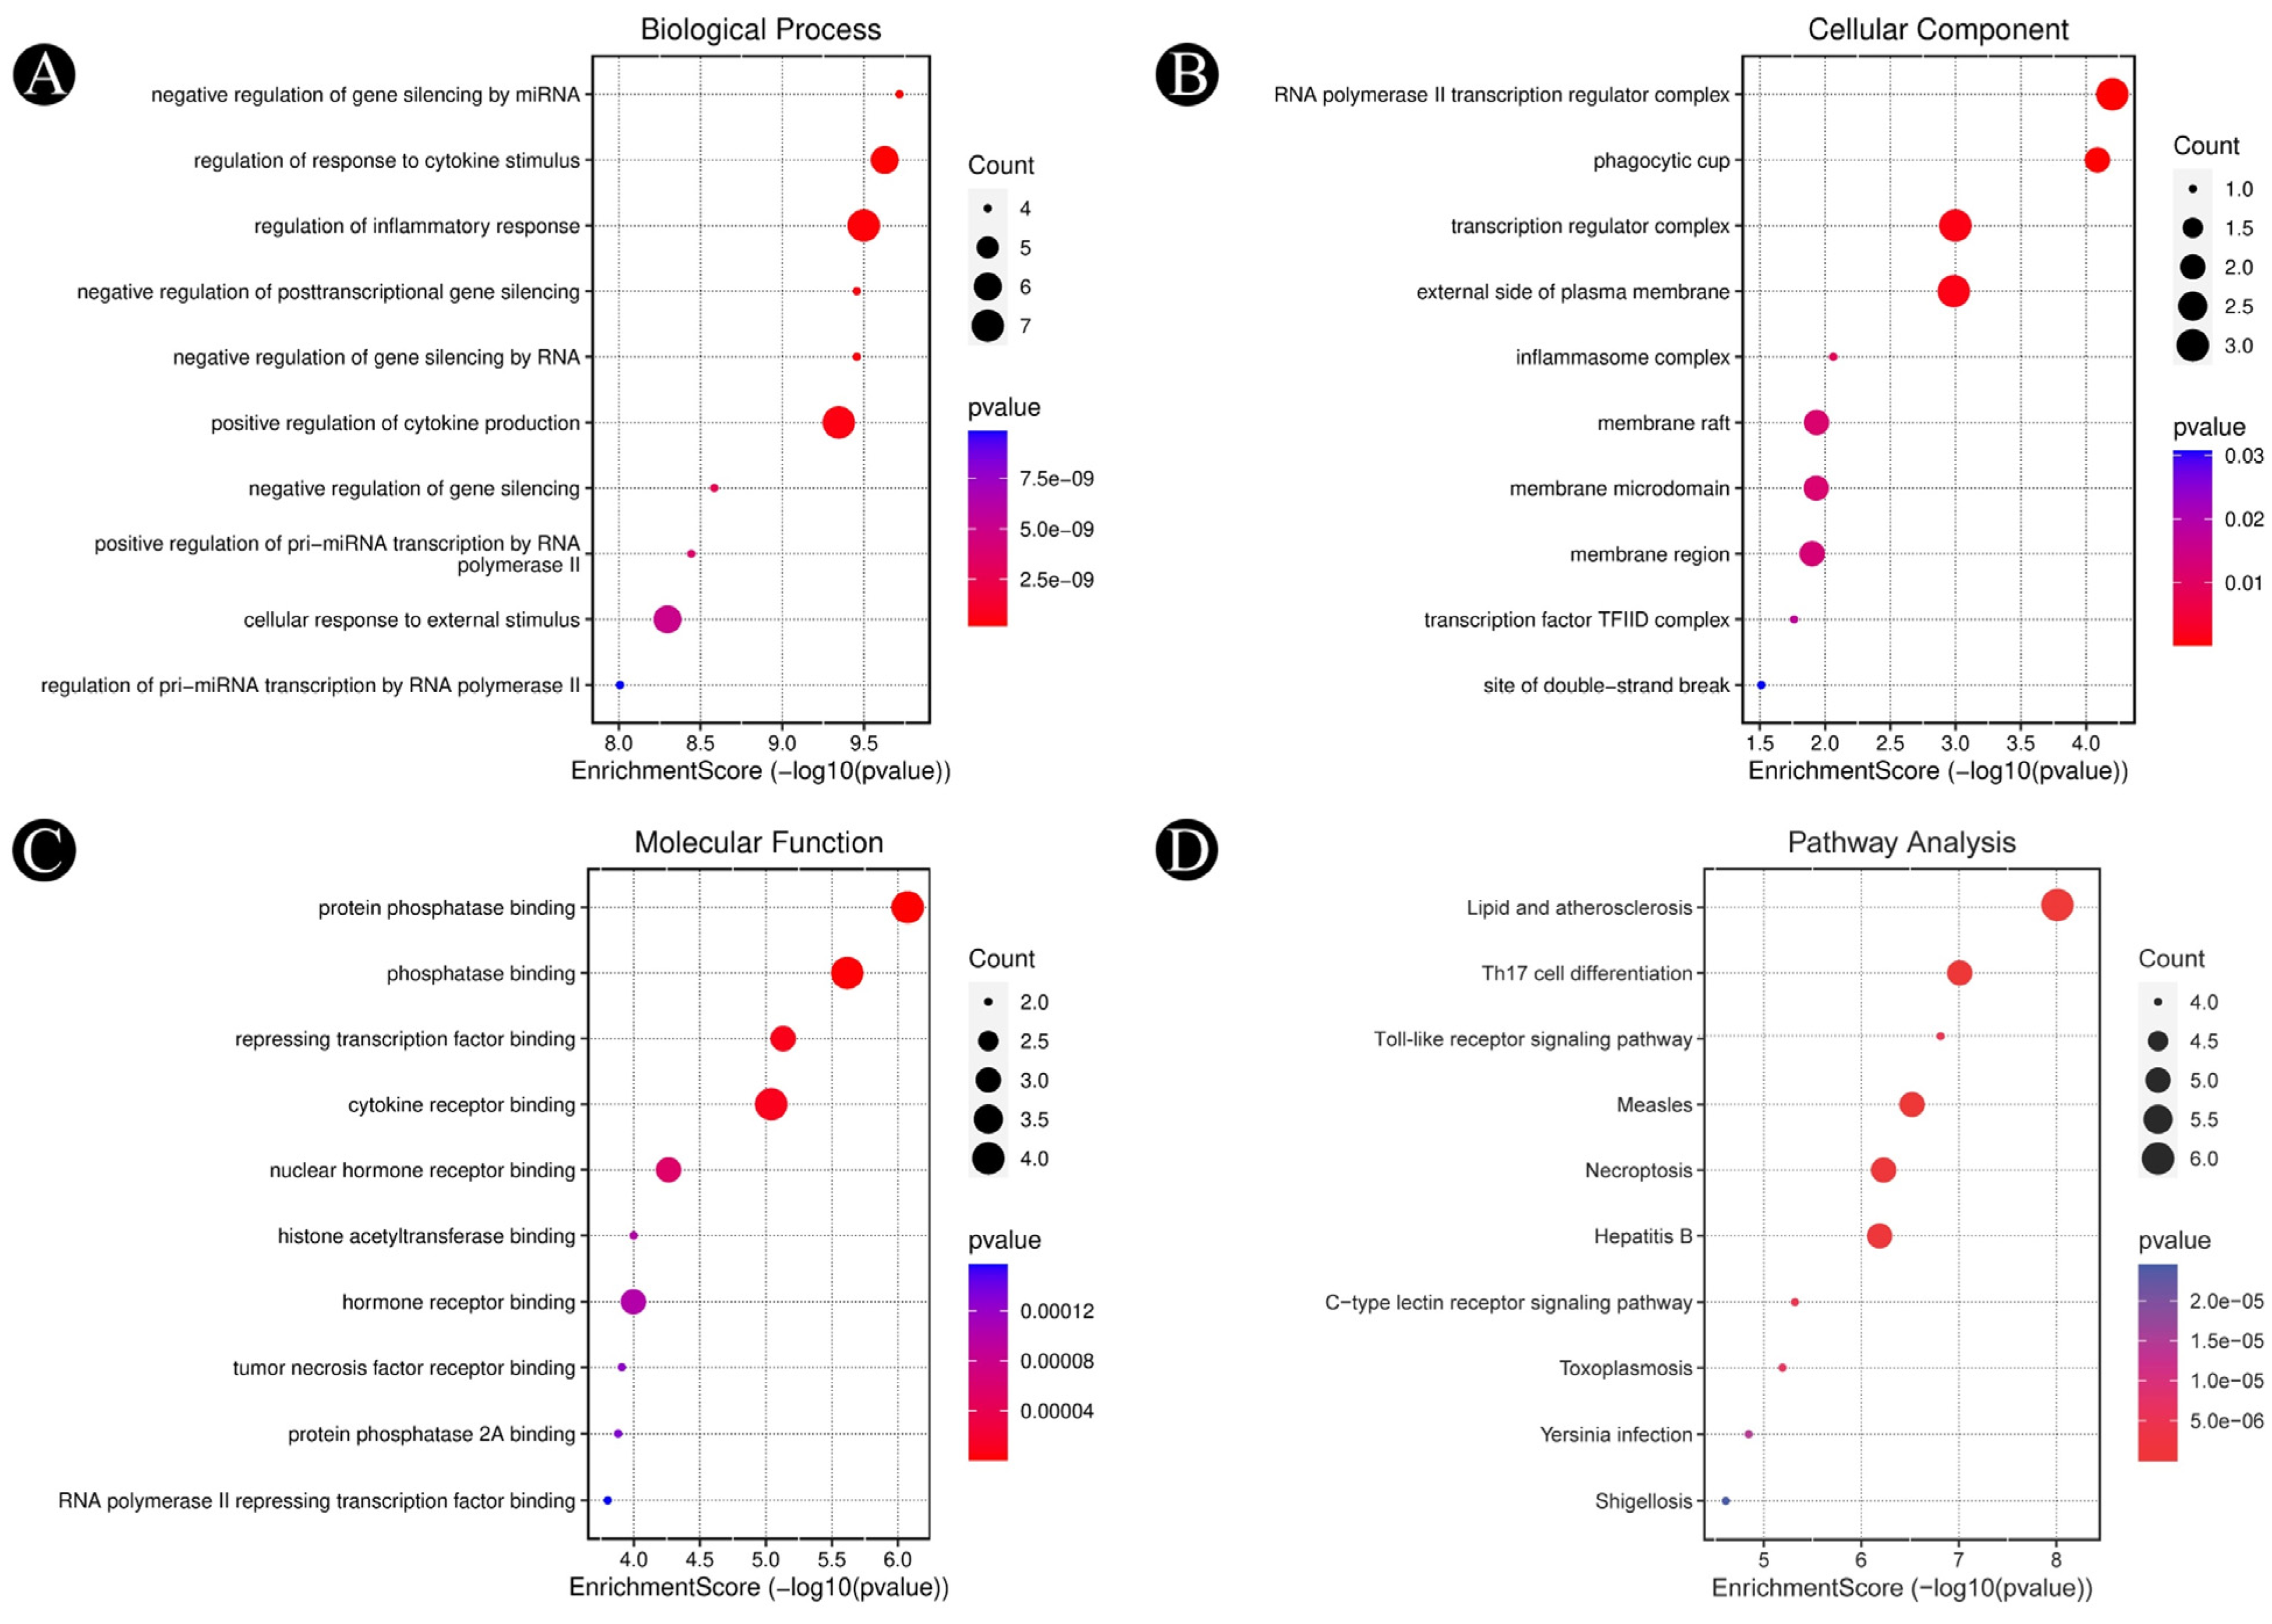

3.3. Analysis of Functional and Pathway Enrichment

3.4. Molecular Docking Analysis